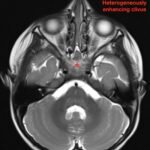

Pediatric neuroblastoma is famously characterized by an abdominal mass in a toddler with “raccoon eyes,” Horner syndrome, and/or opsoclonus myoclonus. However, rare cases may present with non-discrete symptoms and signs which create challenges for timely diagnosis. This case depicts a toddler with bulbar symptoms, including bilateral ptosis, dysphagia, drooling, head tilt and ataxia in a post-viral course mimicking other neurologic diagnoses, including myasthenia gravis. Magnetic resonance imaging (MRI) of the brain and spine uncovered a right adrenal mass along with heterogenous enhancement in multiple vertebral bodies and the clivus, consistent with metastatic disease. A diagnosis of neuroblastoma was confirmed with elevated homovanillic acid (HMA) and vanillylmandelic acid (VMA) levels and adrenal biopsy. The patient was treated with plasmapheresis for suspected paraneoplastic neurological syndrome and subsequent chemotherapy. In this case presentation, we review neurologic syndromes causing acute-onset pediatric bulbar weakness along with the patient’s key MRI findings.